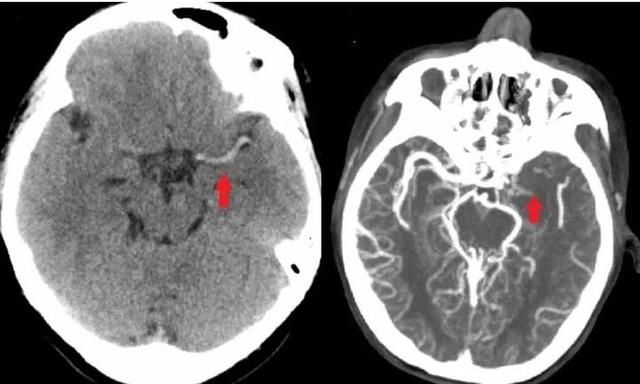

文章图片

CT血管造影显示:章一左侧大脑中动脉血栓形成(上图左箭头所示),导致脑部该区域血流堵塞、血管不显影(上图右箭头所示)。